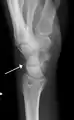

Переломи тригранної кістки трапляються, зокрема, при сильному згинанні зап'ястка, що приводить до відриву її дорсальної частини. Такий відривний перелом часто буває непомітним на фронтальних рентгенограмах, але тонкий фрагмент кістки видно на латеральних.

Перелом тригранної кістки (позначений білою стрілкою).

Перелом тригранної кістки на латеральній рентгенограмі.